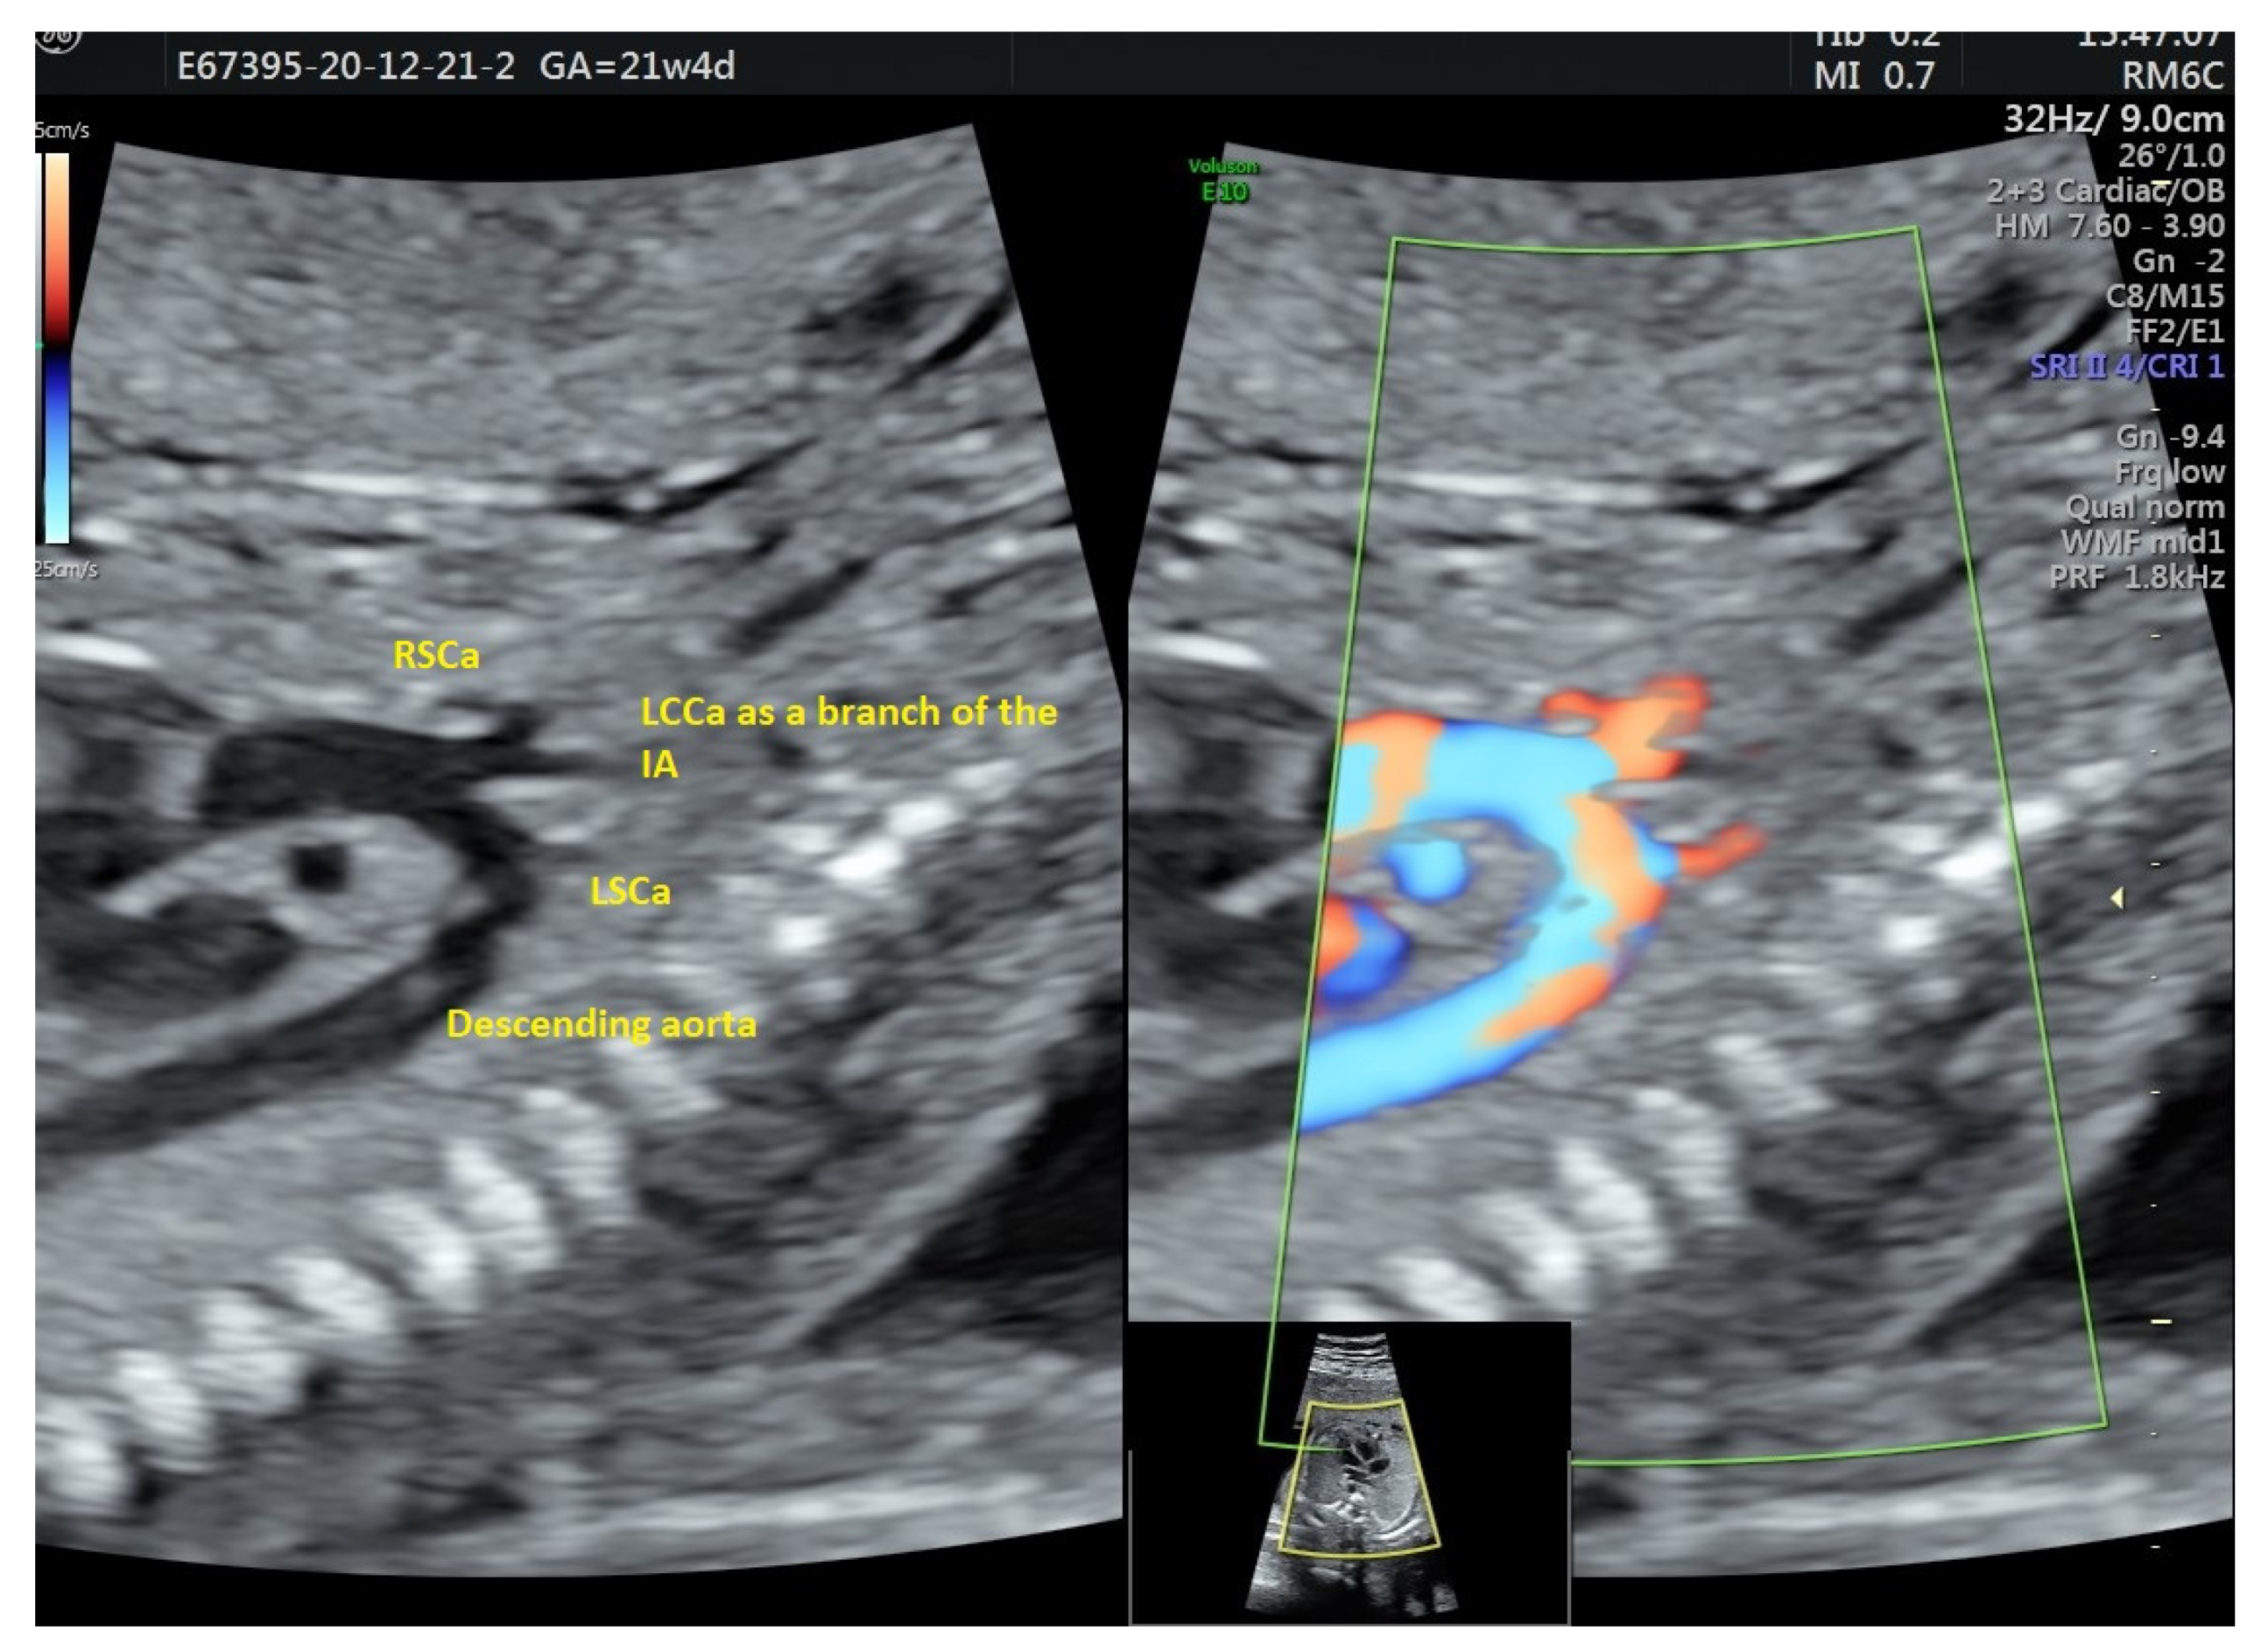

| 31 | 21 + 4 | 1 | type B | none | none | ND | Normal neonatal cardiac scan confirmed AAAV |